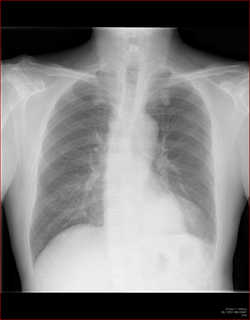

例えば肺の大きさ。

volume

lossや反対に過膨張などの所見は、圧倒的に胸部正面写真がわかりやすいですね。